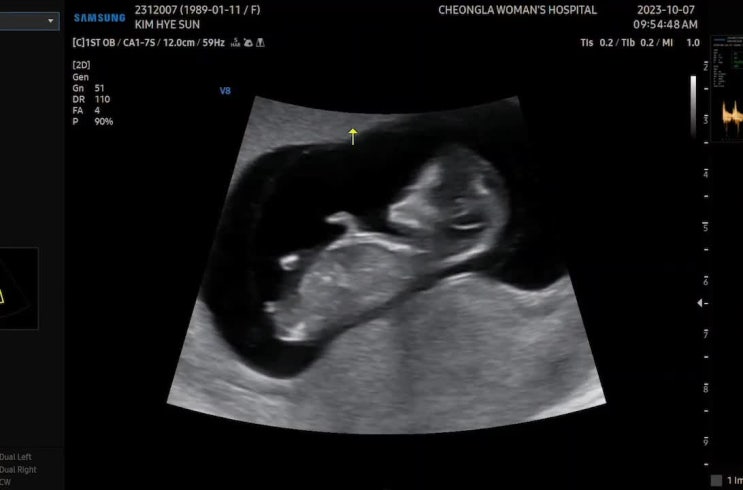

임신26주 임산부 임당검사, 입체초음파 후기

안녕하세요! 드디어 오늘 임당검사 + 입체초음파를 하고 왔어요! 벌써 임신 26주가 되었거든요 ㅎㅎ 왜케 ...